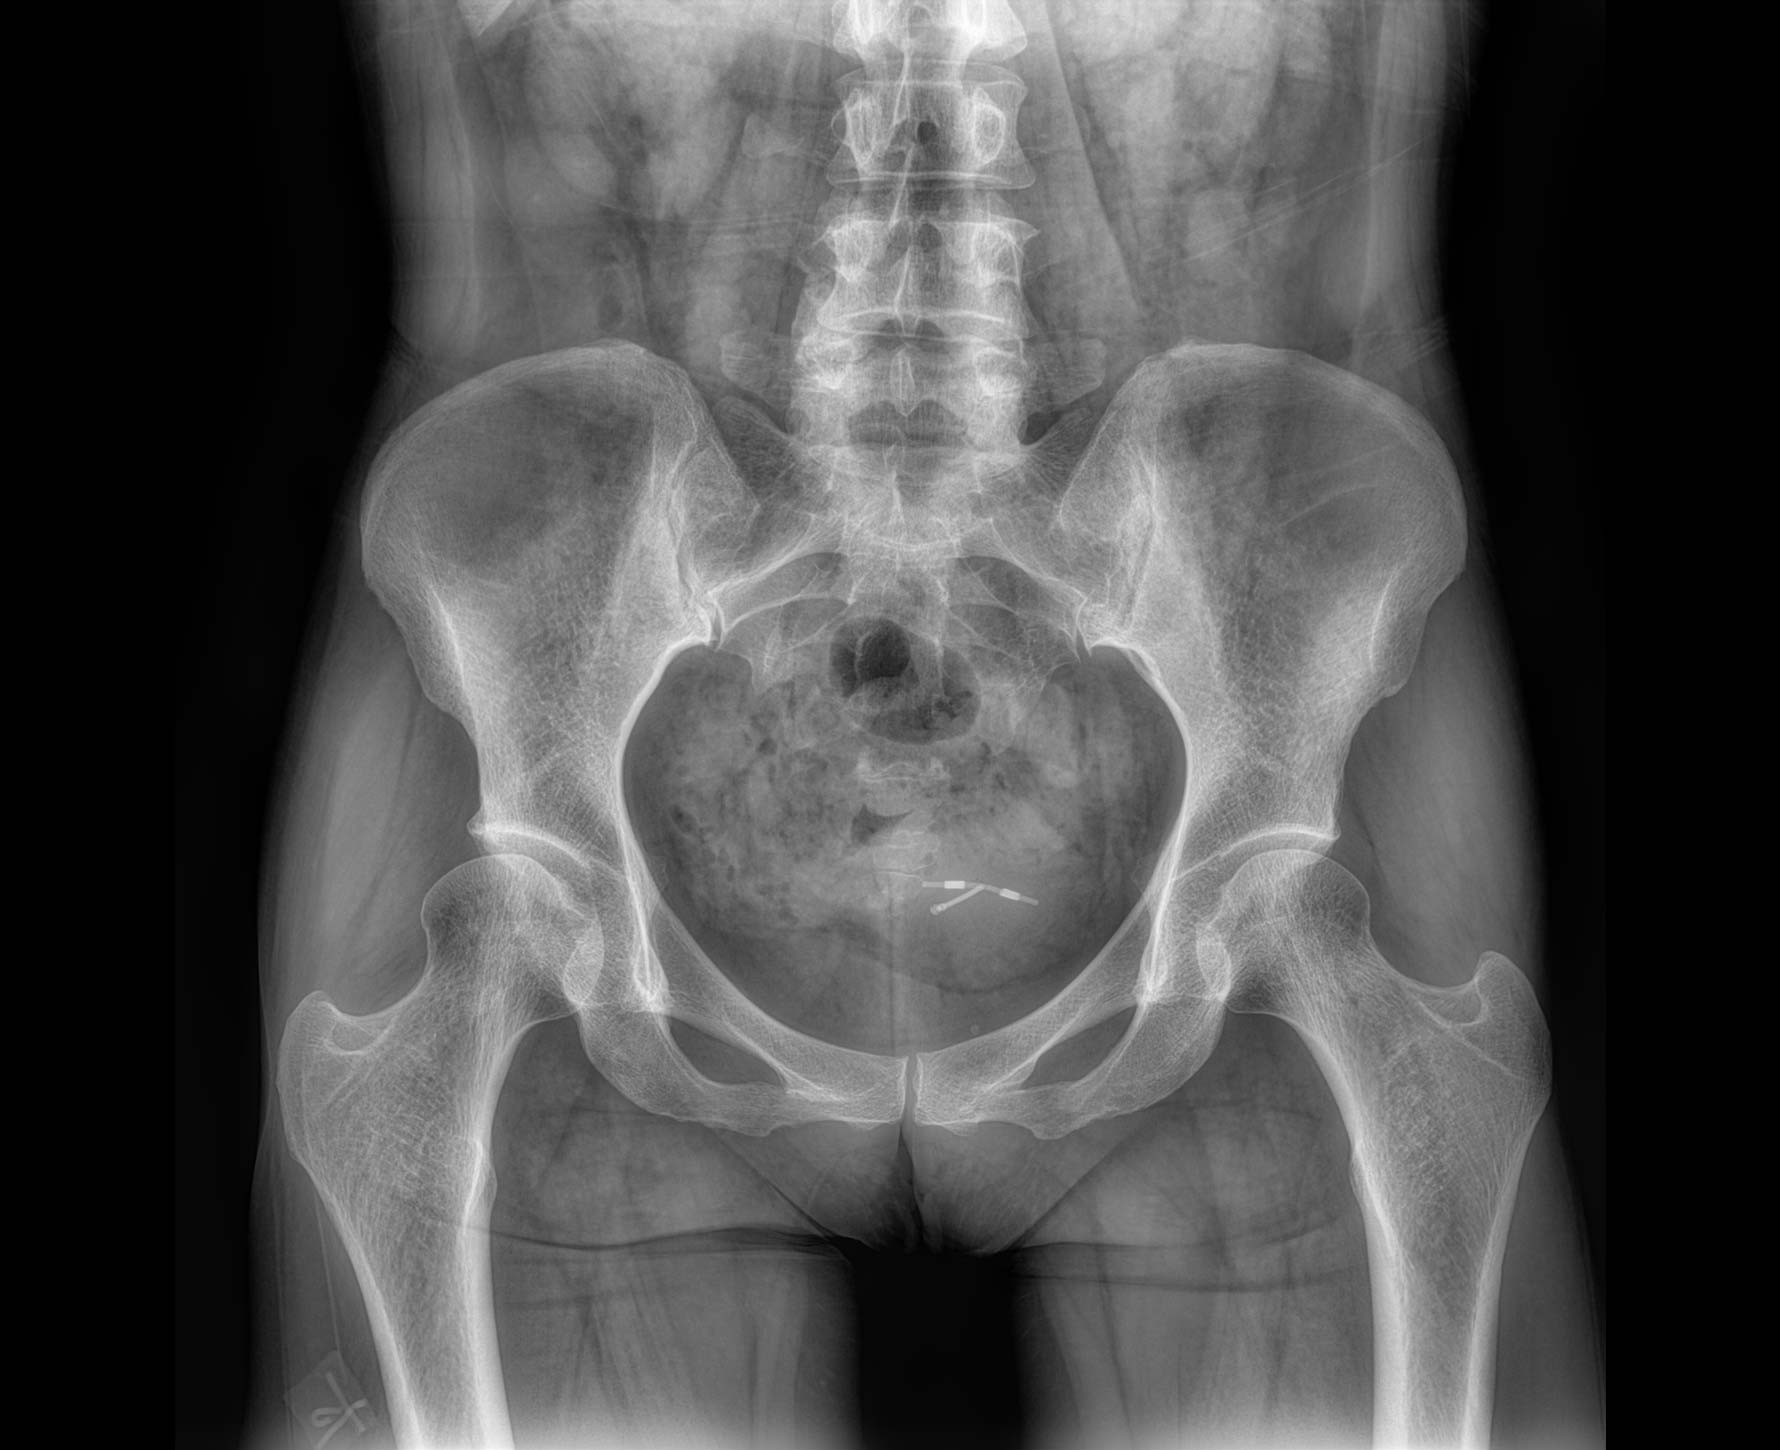

適用于全身各部位攝影

(常規攝影和特殊攝影)

無縫融合處理,保證高質量全景影像。